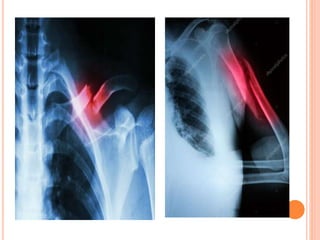

Luxação: Ocorre quando a extremidade do osso é

LUXAÇÃO

 É o deslocamento das superfícies articulares entre

os ossos e lesão das partes moles.

 O cliente apresenta dor intensa, perda das funções,

deformidade e edema progressivo.

 Imobilização provisória da parte afetada e, a seguir,

o tratamento médico - que inclui redução da luxação e

imobilização com gesso.